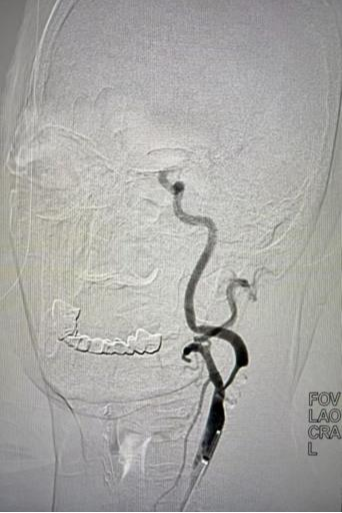

手术当日,血管外科主任汪岩及副主任医师李晓亮凭借丰富的经验与精湛的技术,经股动脉穿刺建立通道。在脑保护装置全程防护下,先使用球囊扩张狭窄部位,随后精准地将支架送至狭窄处并释放,成功撑开闭塞血管,恢复脑部血流灌注。整个手术过程仅留下微小创口,无需全麻开颈。术中,医护人员严密监测患者生命体征变化,确保手术顺利完成。术后造影显示,血管通畅,支架贴壁良好。

▲手术前